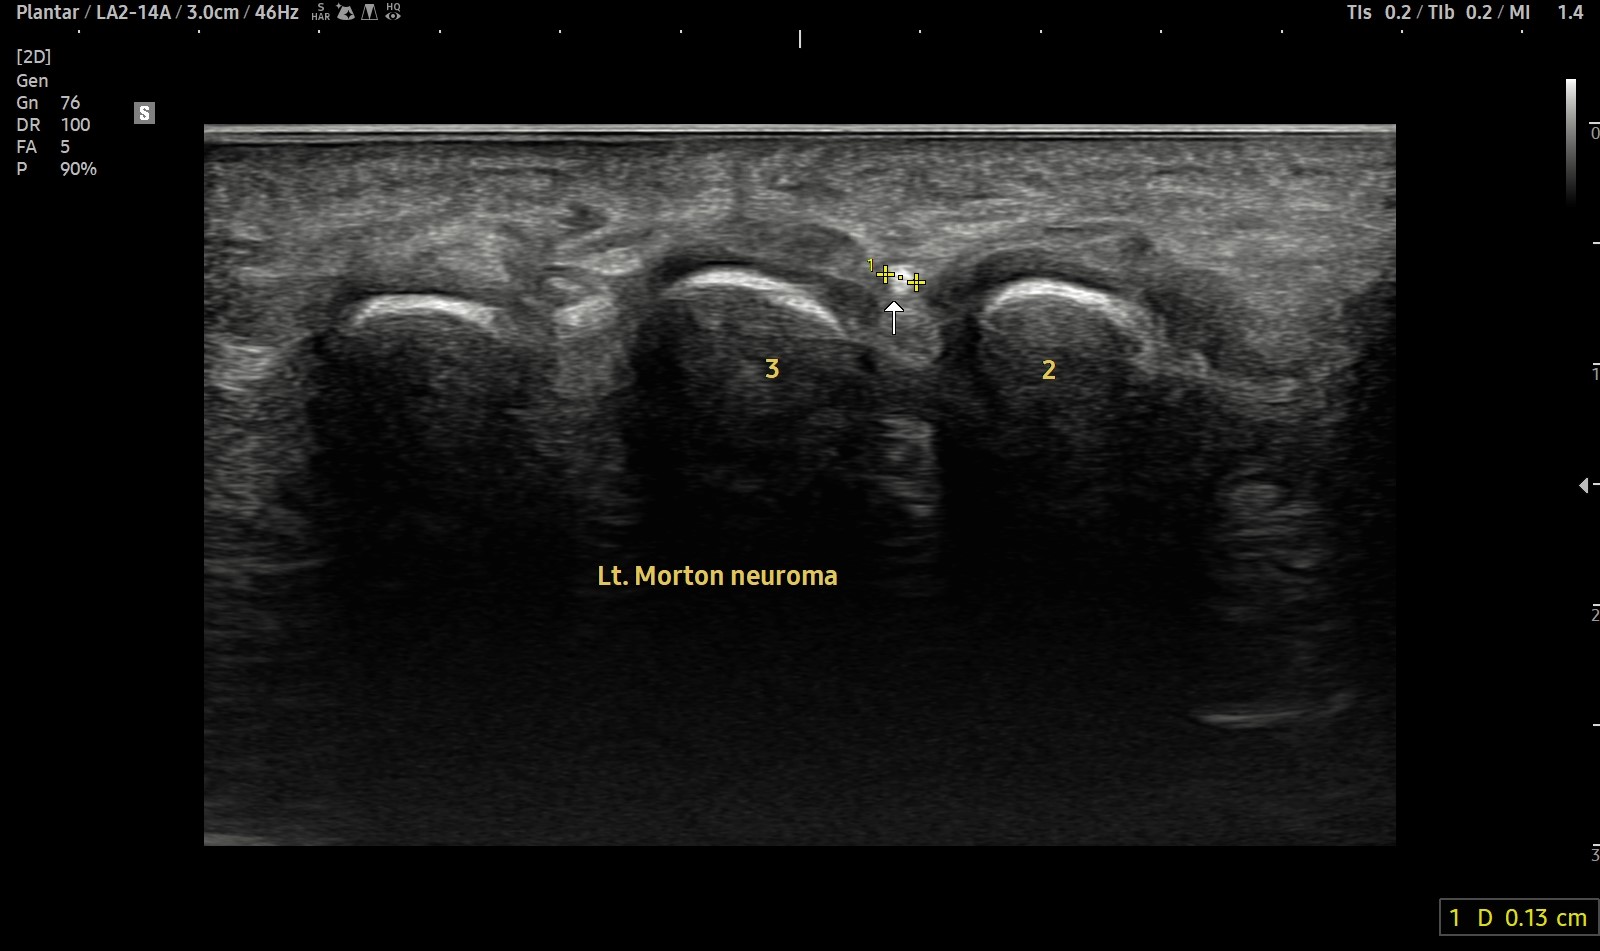

- 치료기간 : 25 . 4 . 1 ~ 25 . 5 26.

- 치료횟수 : 19 회

치료 전

치료 후